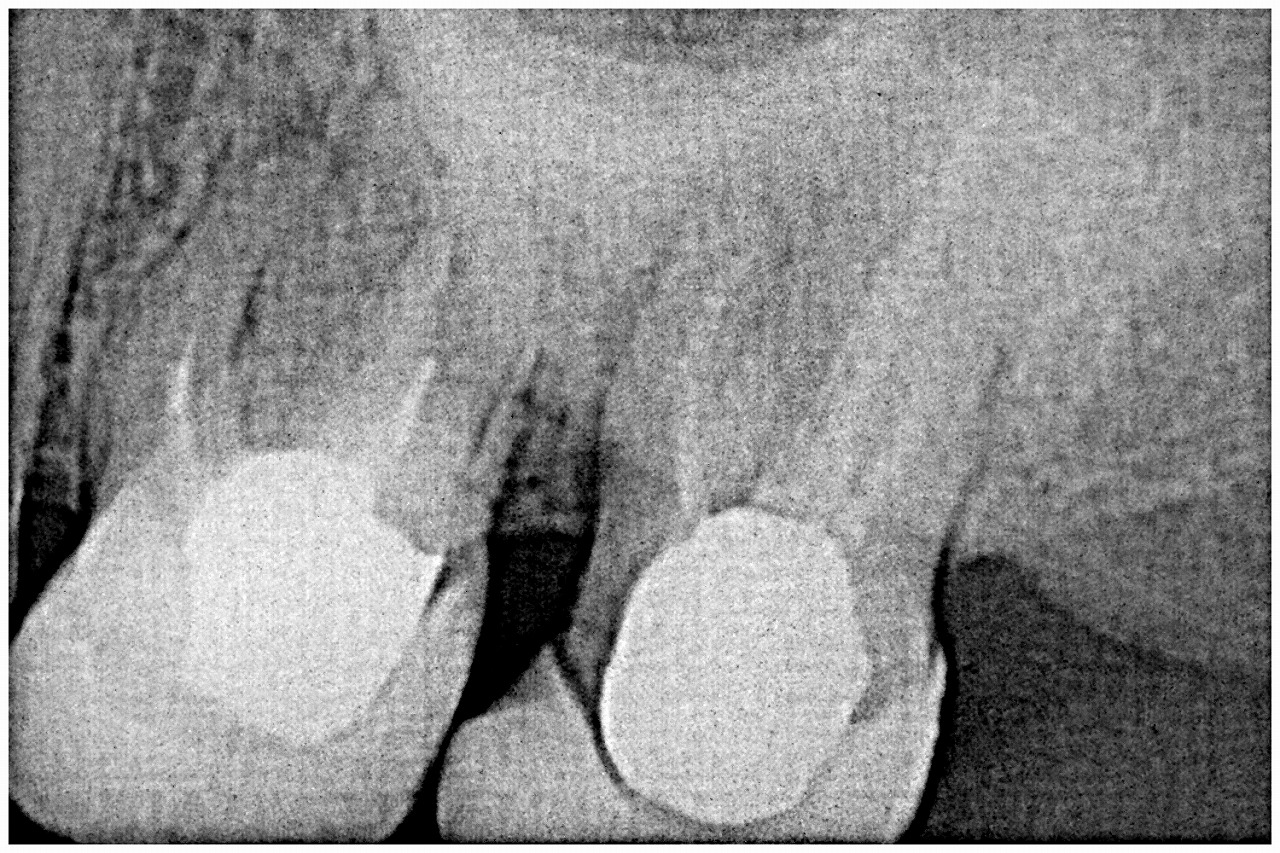

デンタルレントゲンになります

近心根が黒く破折が疑われます

破折が疑われますが補綴を外して確かめていきます